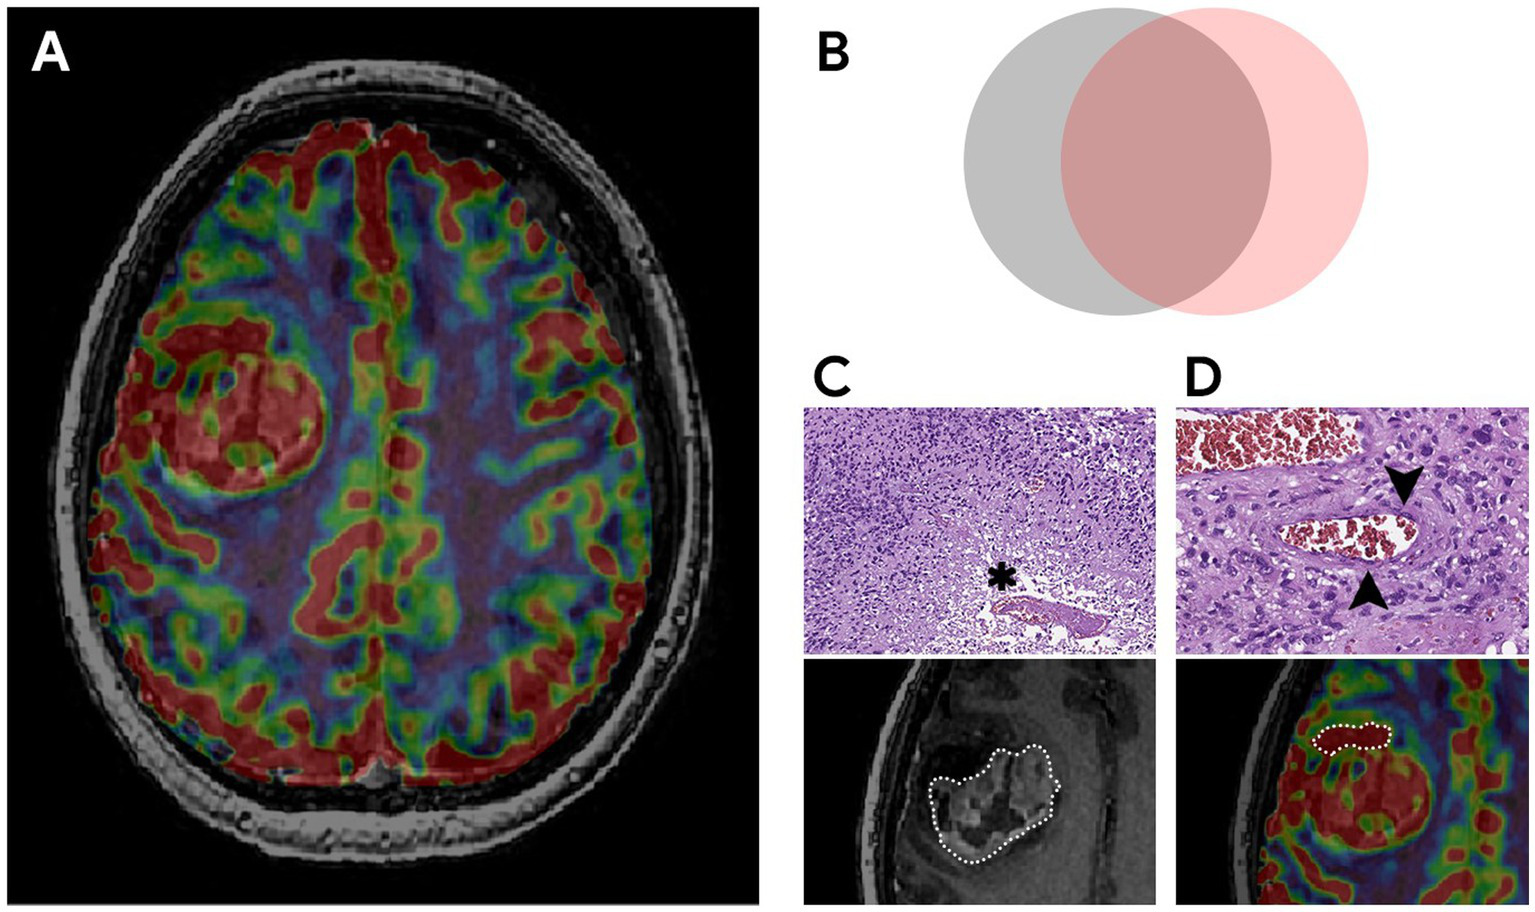

The key factor influencing the prognosis of the disease is the extent of resection of malignant glioma (16–18, 52). It is known that overall survival is associated with total resection (total removal of the contrast-enhancing part of the tumor) which is considered to be a threshold (19). The main prognostic landmark for the effectiveness of the treatment used by neurosurgeons in practice is the residual volume of the contrast–enhancing component of diffuse glioma (20–23). However, some parts of glioblastomas are not able to accumulate the contrast agent and in rare cases, they do not accumulate it at all (24–27). The contrast-positive components of glioblastomas in the post-contrast series reflect the areas with an disrupted BBB which may or may not correspond to the most aggressive part histopathologically (28–32). Besides necrosis glioblastomas have the areas with both the increased proliferative endothelium activity in their structure and an intact BBB (33–36). The intratumoral heterogeneity of glioblastomas and the infiltrative nature of growth make it difficult to assess its boundaries (6, 19, 20, 37, 38). Surgery aimed at only resection of the contrast-enhancing part of the tumor is attended with the risk of early relapses. Implemented perfusion methods using CT and MRI have a unique ability to identify the areas with the vascular proliferation using noninvasive biomarkers of tumor hemodynamics (TBF, TBV, nTBF, nTBV). There are a number of studies examining the blood flow of a tumor in the most malignant areas (13, 39, 40). The aim of the current study is to estimate the contrast-positive and hyperperfused contrast-negative components of glioblastomas for preoperative resection volume planning. In our study data obtained are accomplished with the help of CT and MRI perfusion techniques. Perfusion parameters are taken into account both in contrast-positive components of gliomas and in components without the contrast accumulation. Besides the main stage of the tumor resection matching preoperative perfusion data including histological and immunohistochemical ones taken from the sampled tissue having the regions of interest and their interconnection is performed (Figure 10). All the samples obtained from the zone which do not accumulate the contrast agent are infiltrated by tumor cells without damage to the BBB which demonstrates the importance of perfusion CBF and CBV parameters in the contrast-negative zone and does not contradict the previously published works concerning the most malignant areas (23, 39, 40, 53).

Figure 10

The most aggressive morphological components of glioblastoma, their relationships and pathological substrates. (A) MRI of the brain of a patient with right frontal lobe glioblastoma. Compared post-contrast T1 WI and CBV perfusion map, demonstrating a large contrast-enhancing component and areas with high TBV located inside and outside the high signal on the post-contrast T1 WI. (B) Schematic representation of the relationship between malignant components. The gray circle represents a tumor component with a disrupted BBB (the part of the tumor that accumulates contrast). The pink circle reflects the tumor component with microvascular proliferation (the part of the tumor with high TBV values). The overlap of both components represents the largest area which is coded in ivory color. The study focuses on the part with high TBV values located outside the contrast accumulation (part of the pink circle) and the investigation of the effect of its resection along with the contrast-enhancing portion on the duration of the recurrence-free period. (C,D) Histological examination, magnification × 10, staining with hematoxylin and eosin. Comparison of MRI data with microscopic substrates of glioblastoma radiological features. (C) The upper figure shows tumor cells with nuclear atypia and a large area of necrosis (asterisk), corresponding to the area of accumulation of contrast in the lower figure. The lower figure is a post-contrast T1 WI, a component of a glioblastoma with a necrosis cavity (the area highlighted by the dotted line). (D) The upper figure dipicts the proliferation of the endothelium of the tumor vessel (arrows), which causes high TBV values on the CBV perfusion map (lower figure). The lower figure is a CBV perfusion map, the area highlighted by the dotted line is located outside the contrasted part of the tumor.